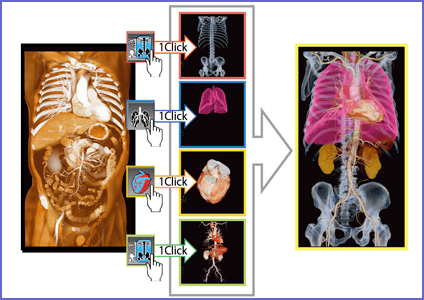

お得な情報満載 ラットの断面解剖アトラス 出版事業 - 医学一般